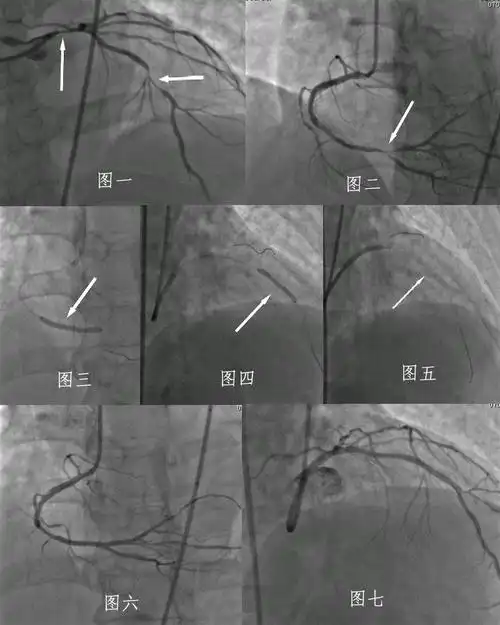

正常冠脉造影和冠状动脉支架植入术图解